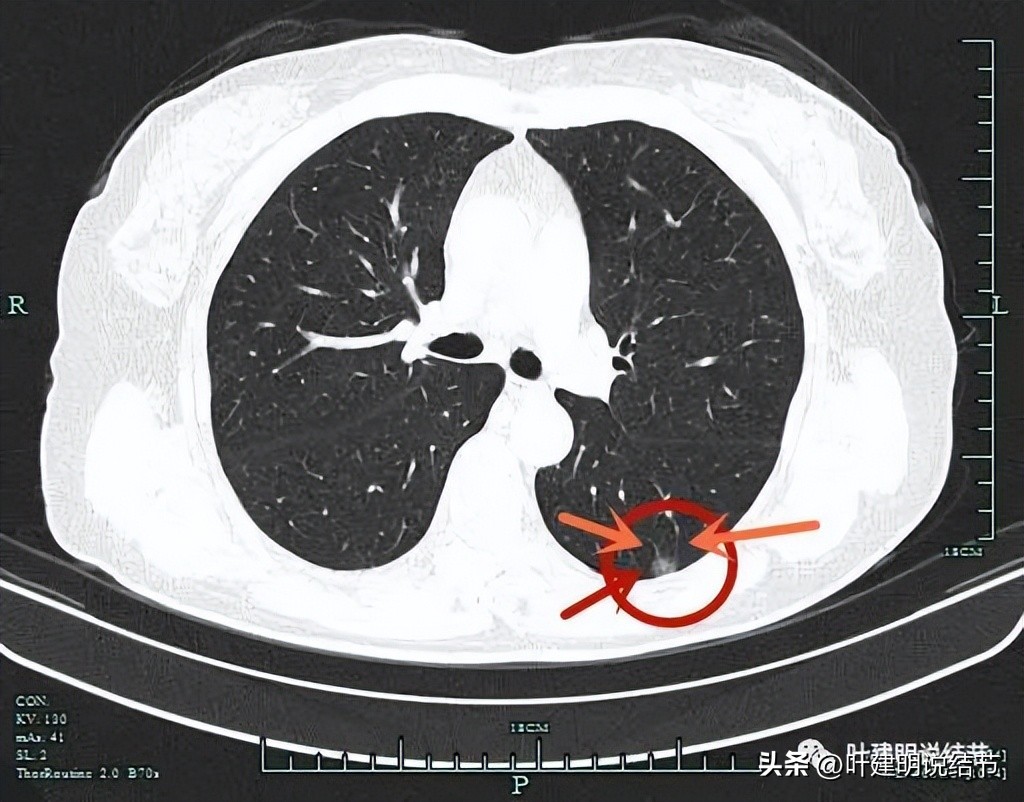

影像特点:

右下叶这个病灶紧邻叶间胸膜,但没有明显胸膜牵拉,说明收缩力不强,良性可能性大些。但随访持续存在,周围肺野清晰。部分似有点像磨玻璃密度,中间有空泡征。这种密度的结节,又不是结核好发部位,半年了没有吸收好转,即使进展不显著,也不放心。